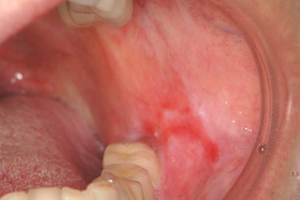

72歳女性 フコイダン有効例 (右側紅板症)

フコイダン投与 前日 BEFORE

フコイダン投与 1ヶ月後 AFTER